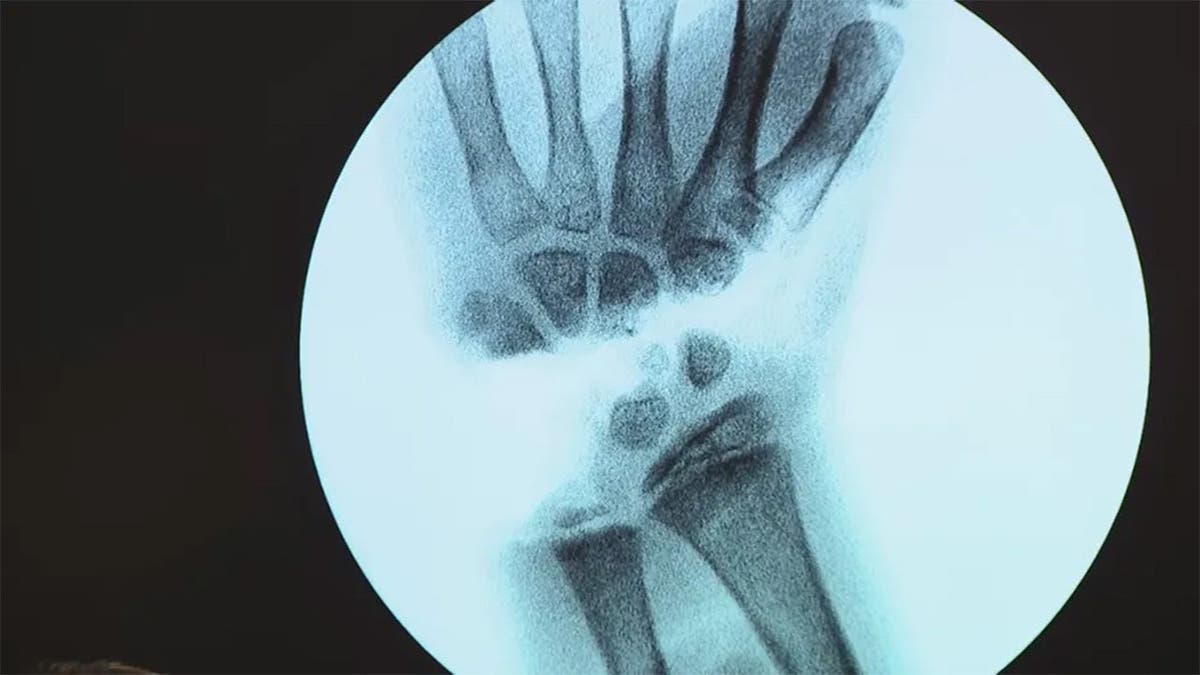

Leah Lendel's X-Ray

Leah Lendel was airlifted to Tampa General Hospital following the shark attack, where she underwent surgery that lasted hours while doctors worked to save her hand. (WTVT-TV)

Surgeons were able to successfully reattach her hand following the attack. Leah, now 10, is still working to regain her strength day-by-day.